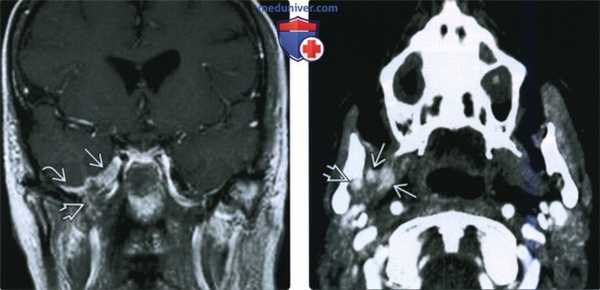

(Слева) На корональной МРТ (Т1 ВИ С+) у этого же пациента определяется ПНО ЧМН V3 с распространением через овальное отвераиев меккелеву полость и кнаружи вдоль твердой оболочки в средней черепной ямке.

(Справа) На аксиальной КТ с КУ у этого же пациента визуализируется контрастирующаяся опухоль в нижнечелюстном отверстии справа наряду с патологическим контрастированием нижнечелюстной ветви V3 в жевательном пространстве.

(Слева) МРТ Т1ВИ с КУ, коронарная проекция, этот же пациент. По нижнечелюстному нерву опухоль распространяется в овальное отверстие и тройничную полость. Также опухоль прорастает латеральнее, в твердую мозговую оболочку средней черепной ямки.

(Справа) КТ с КУ в аксиальной проекции, этот же пациент. В области правого отверстия нижней челюсти определяется накапливающая контраст опухоль. В жевательном пространстве видны участки аномального накопления контраста вдоль волокон нижнечелюстного нерва.

(Слева) КТ в костном окне, аксиальная проекция. По сравнению с нормальным левым овальным отверстием правое овальное отверстие увеличено в размерах. Расширение отверстия обусловлено распространением злокачественной опухоли по нижнечелюстному нерву.

(Справа) КТ с КУ, аксиальная проекция. По волокнам нижнечелюаного нерва опухоль распространилась в тройничную полость и среднюю черепную ямку. Обратите внимание, что с левой стороны тройничная полость имеет нормальную плотность, соответствующую плотности спинномозговой жидкости.